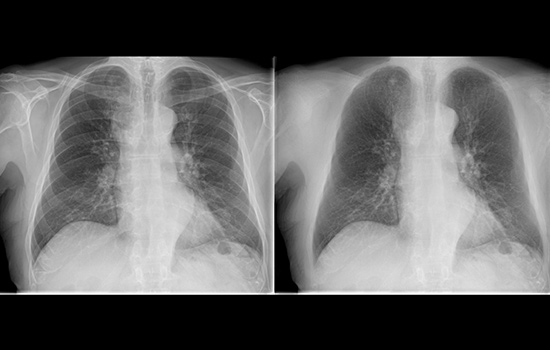

Compare side-by-side with a conventional image processing and see the benefits for yourself.

フィリップスのマルチ周波数処理UNIQUE2と胸部骨減弱処理Bone Suppression*²で、より確信のもてる画像診断をサポート。 肺結節の検出率を16.8%*³3向上します。